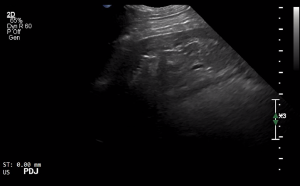

SIMON Ultrasound Database

This ultrasound database is a free resource for students and doctors!

Our collection includes videos of dogs, cats, horses, cows, humans, and many other species!

–Canine and Feline abdominal ultrasound videos were generously provided by the Cummings School of Veterinary Medicine at Tufts University.